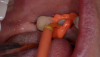

Figure 2: Example of a VPS impression.

Figure 2

VPS materials are the author’s preference for restorative impressions (Figure 2). Many VPS impression materials are on the market, and they are available in a wide variety of viscosities and set times to suit the clinician’s preference. In general, they are stable over time and accurate, and allow multiple pours and set times.5-7

Because they are hydrophobic, keeping the surface completely dry is important,8 as is tissue retraction—which has nothing to do with the hydrophobic nature of the material—and there are choices of viscosity/consistency in tray materials. As noted in the technique discussion below, the author prefers to use a plastic disposable tray.